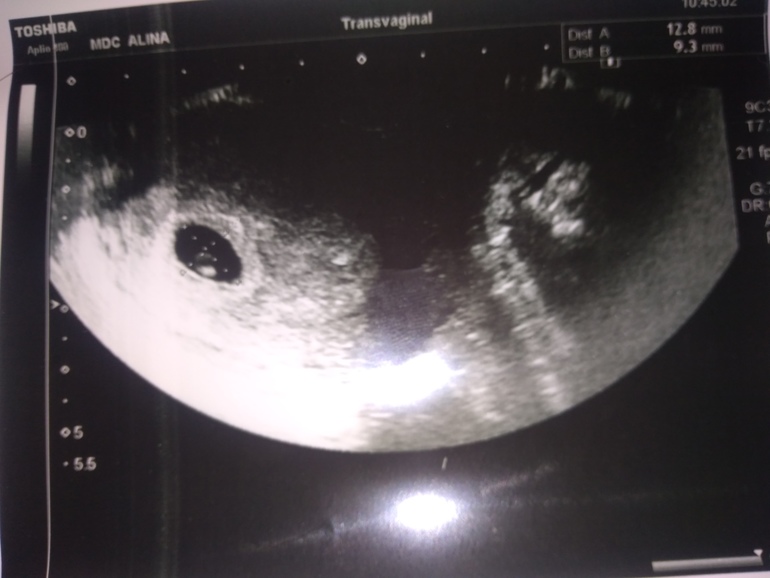

Первое УЗИ💕💕💕

Беременность- 1 триместр ( только до 10 недель)Не выдержала, сбегала на УЗИ

Увидели плодное яйцо и эмбриончик.

Сердечко пока не услышали. Сказали , через недельку уже будет слышно💕💕💕

Единственное, поставили срок 5 недель и 6 дней.

А по месячным у меня выходит 6 недель и 2 дня.